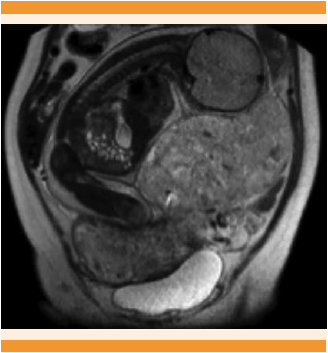

Paciente de 35 años, con IMC de 35.4, en su tercer embarazo, con antecedente quirúrgico de dos cesáreas por desproporción céfalo-pélvica. Negó enfermedades de transmisión sexual. Acudió a consulta médica por dolor abdominal y amenorrea de aproximadamente 5 meses de evolución, con un único episodio de sangrado leve. El ultrasonido ginecológico mostró vacía la cavidad uterina, por lo que el dolor fue adjudicado a una hernia umbilical y se programó para cirugía. Durante los meses siguientes tuvo episodios intermitentes de dolor abdominal, por lo que acudió nuevamente a consulta. A la exploración física se identificó una masa abdominal, que abarcaba el epigastrio, mesogastrio hipocondrio y flanco derechos. El ultrasonido no reportó datos concluyentes. Se mantuvo hemodinámicamente estable, por lo que fue enviada al Hospital Civil de Guadalajara Fray Antonio Alcalde para posterior estudio, debido a la sospecha de embarazo ectópico. La resonancia magnética confirmó el embarazo abdominal de término (Figura 1). Debido al aumento del dolor abdominal y al sangrado transvaginal se decidió la interrupción del embarazo por laparotomía, donde se observó la bolsa amniótica después de la incisión abdominal (Figura 2); la placenta se encontraba adherida a la superficie serosa del fondo uterino, el útero no mostraba signos de aumento de tamaño; no se encontró la trompa de Falopio izquierda, por lo que se asumió que ésta fue el sitio de implantación inicial. Se efectuó la ruptura transquirúrgica de membranas, con salida de líquido meconial (+++) y de la cirugía se obtuvo un neonato adinámico (Figura 3). Se iniciaron maniobras de reanimación, mediante ventilación con presión positiva y se valoró un Apgar al primer minuto de 6, a expensas de llanto irregular, acrocianosis, tono disminuido y poca respuesta a los estímulos. Se aplicó un segundo ciclo de ventilación con presión positiva, con el que se obtuvo un Apgar a los 5 minutos de 8, a expensas de acrocianosis y tono disminuido. En la exploración física no se observaron alteraciones musculoesqueléticas; las somatometrías estuvieron en el percentil 90 para peso, talla y perímetro cefálico. Se estimó una edad gestacional de 42.5 semanas por método de Capurro. Después de ligar el cordón umbilical se practicó la hemostasia placentaria, ligando los vasos más accesibles y procediendo a dejar la placenta in situ, debido al riesgo elevado de hemorragia por su remoción, por lo que en ese momento se dio por finalizado el tiempo quirúrgico. El neonato fue enviado a la unidad de cuidados intensivos neonatales para vigilancia, manteniéndose estable con oxígeno suplementario (Figura 4). Durante su estancia tuvo un episodio de taquipnea transitoria, por lo que se inició apoyo ventilatorio con presión positiva continua en la vía aérea durante 6 días y posteriormente con oxígeno suplementario. Debido a la detección de un soplo protosistólico, intensidad 2 de 6, se realizó el ultrasonido cardiaco, que no reportó alteraciones. La madre no recibió tratamiento con metotrexato, se recuperó adecuadamente durante el periodo posquirúrgico, para después recibir tratamiento con analgesia y deambulación temprana. La madre y su hijo se dieron de alta el décimo día de hospitalización, ambos sin mostrar datos patológicos y con cita médica después de un mes del procedimiento quirúrgico para seguimiento.